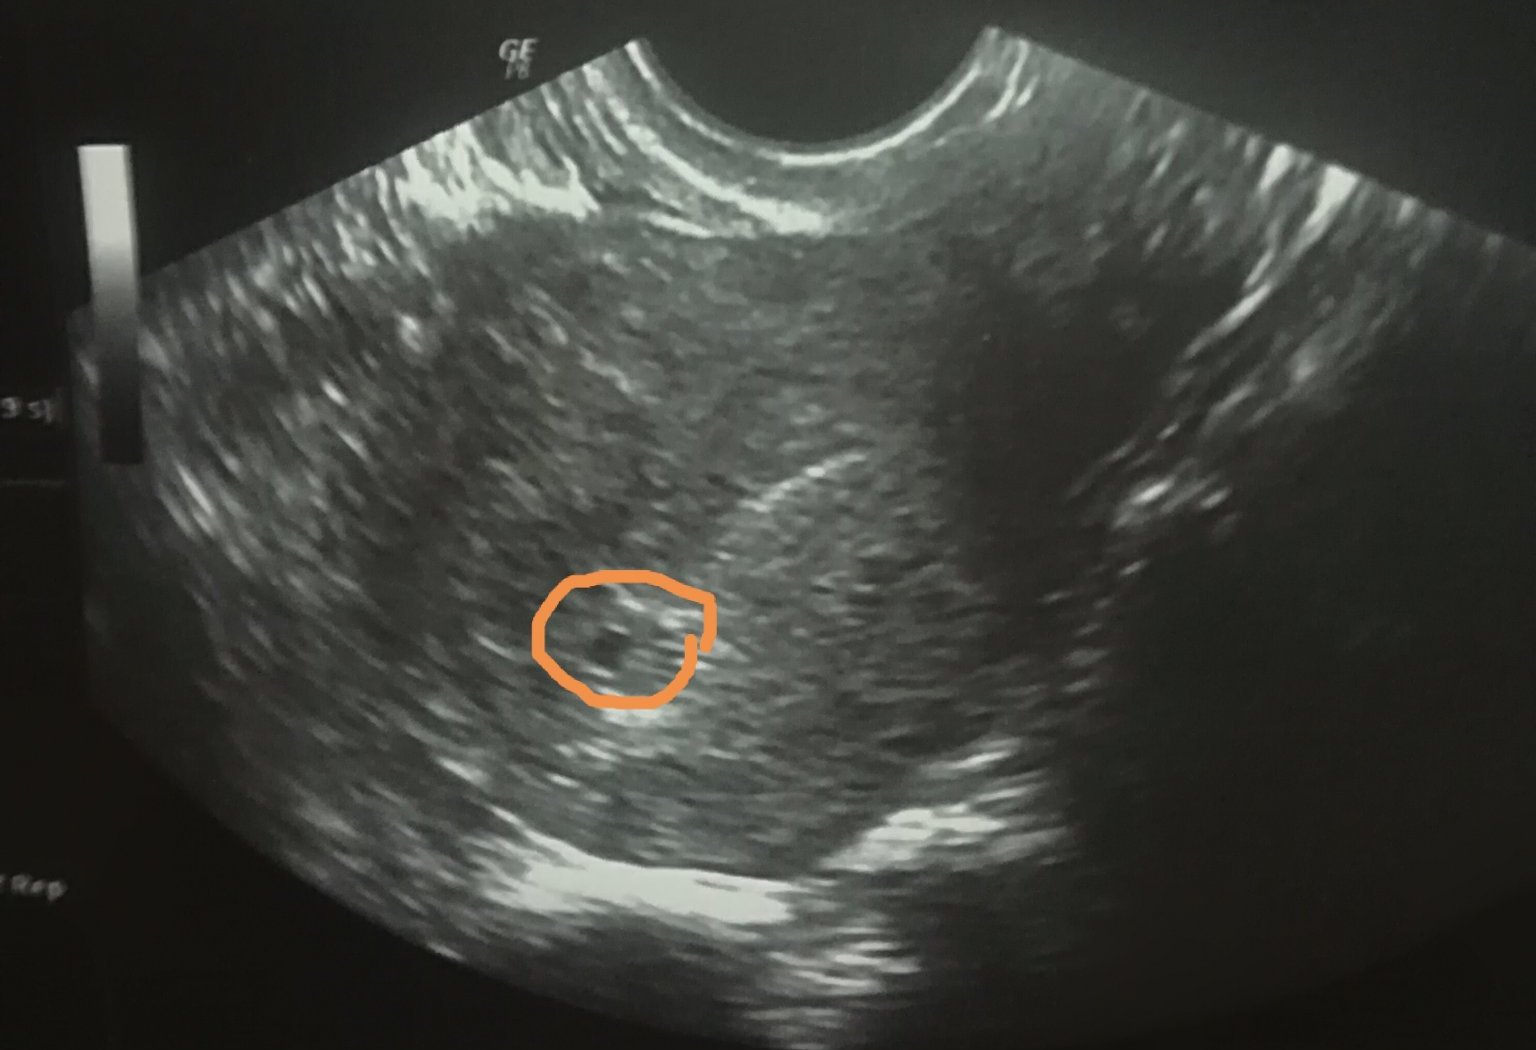

Кога може да се види нещо при коремна ехография?